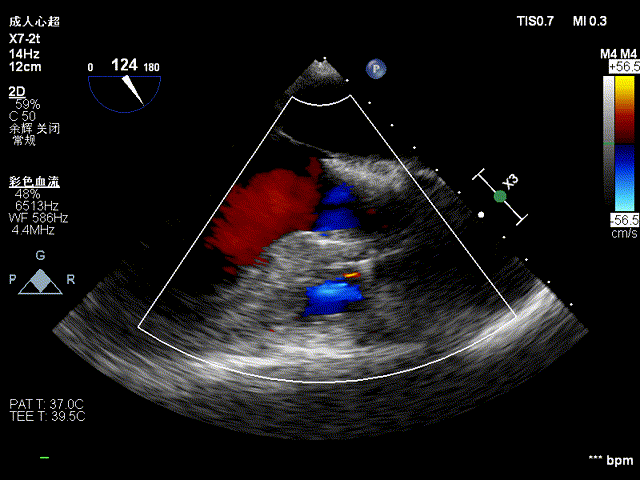

超声显示:升主动脉34mm、窦部34mm,左房(前后/横径) 41/40mm,左室(舒张期/收缩期)58/37 mm,EF 66%。彩色多普勒显示主动脉瓣和二尖瓣反流。

超声提示:左心增大;心脏瓣膜病,主动脉瓣中重度关闭不全,二尖瓣中度关闭不全。

术前超声见主动脉瓣反流:

二尖瓣中大量反流: